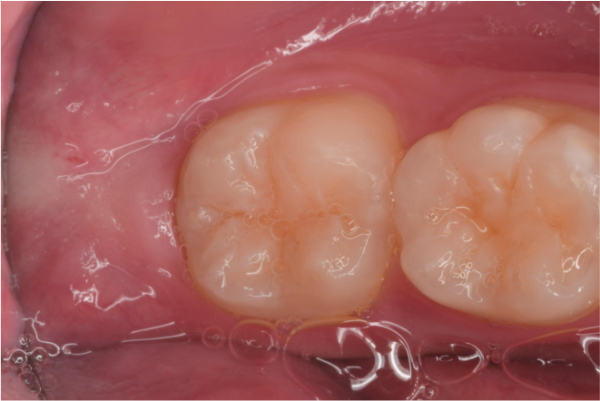

治療前,左下阻生齒深度蛀牙